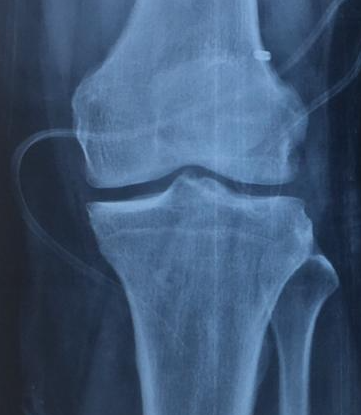

PROFILE TRAINING AND PRESENTATION Dr. Niranjanan Recieving Diploma SICOT degree in Rome, Italy Dr. Niranjanan being awarded fellowship certificate at Indian spinal injuries centre CLIINIC SOME OF Dr. NIRANJANAN's CASES